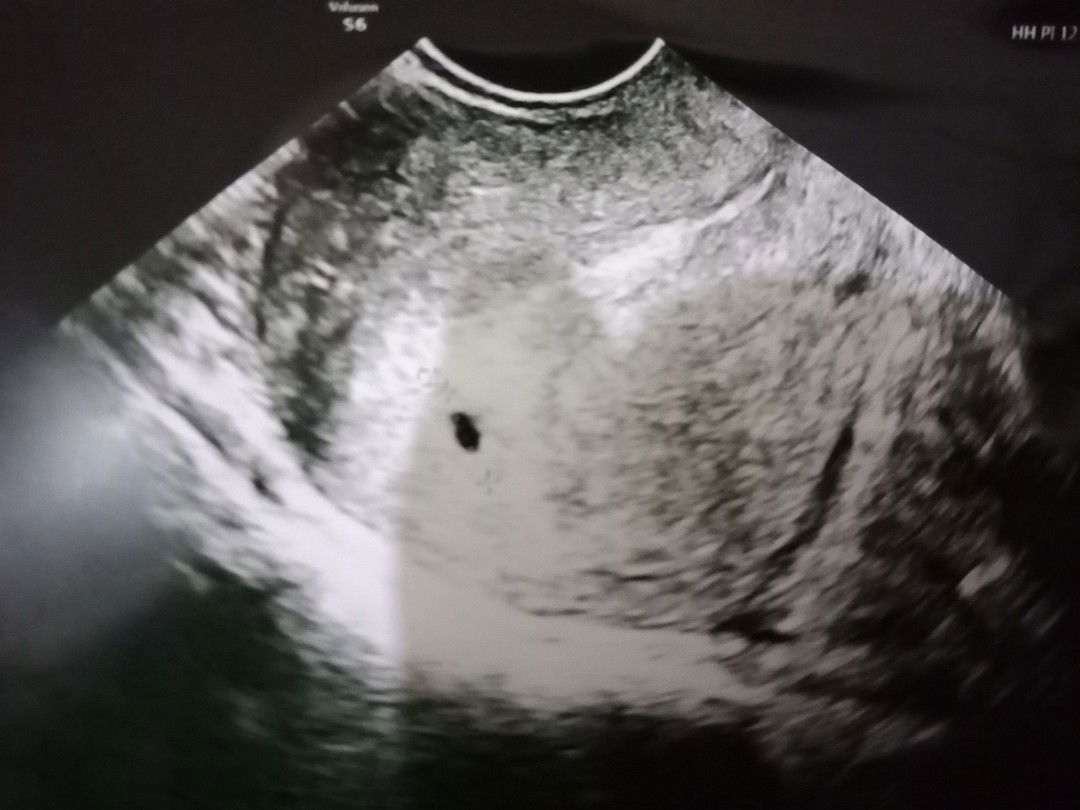

normalkah?

Hamil 5 weeks di USG yg terlihat masih kantung janin, janinnya belum terlihat. Dokter minta saya balik lg 2 minggu kemudian untuk di cek. Apakah ada yg pernah mengalami bun? Apakah itu normal ? Kapan janin biasanya akan terlihat?

Normal bun...saya dulu 6w masih kantong jg...2 minggu lg ikuti saran dokter buat usg...semoga kehamilan nya lancar bun